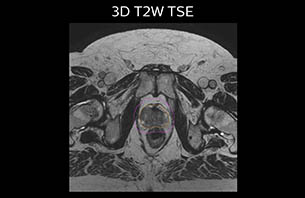

A 77-year-old male with prostate cancer cT3aN0M0, Gleason 8 and PSA 52 μg/L referred to androgen deprivation and radiation therapy with a prescribed dose of 50 Gy to the pelvic lymph node regions and 76 Gy to the prostate.

MR-only simulation workflow The 3D T1W FFE mDIXON sequence provides in-phase, water and fat images in one acquisition. Target and organs-at-risk are delineated on the 3D T2W TSE images. Prostate GTV is shown in orange, PTV in purple. The 3D bFFE sequence is used by the planner to mark the position of the fiducial markers (gold anchors) and contours are transferred to the digitally reconstructed radiographs (DRRs).

Based on the 3D T1W mDIXON images, MR-based density maps (MRCAT) are automatically generated. The VMAT (Volumetric Modulated Arc Therapy) plan is generated in TPS, based on MRCAT as primary image set. During the commissioning phase, dosimetric agreement between MRCAT-based and CT-based dose plans was studied and differences in the PTV dose were found to be minimal (<1% for most patients). Average difference in PTV mean values was 0.8% over the study group (n=62).